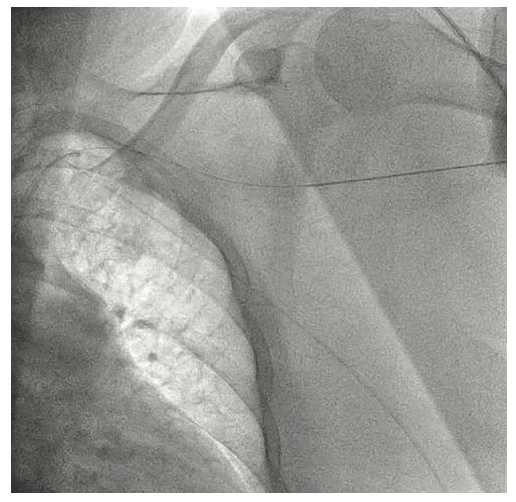

The right groin was accessed using fluoroscopic guidance. A micropuncture sheath was placed and upsized to a 7 French, 45 cm Destination sheath (Terumo) in the right groin. We accessed the right radial, but could not get good flow. Therefore, we ended up using the ulnar artery with ultrasound guidance and placed a Terumo 5/6 Slender sheath in the ulnar artery. We proceeded to access the left axillary artery. We placed a Judkins right (JR)4 catheter in the left subclavian and did a selective angiogram, documenting the location of the thoracoacromial artery and circumflex humeral (Figure 4); then using a Chiba biopsy needle (Cook), accessed the axillary artery and placed a 5-French 30 cm sheath (Cook)(Figure 5). We used the 15 cm biopsy needle to allow us a shallow angle of approach with the patient’s body habitus and to avoid “kinking” the sheath. We then switched out for the Lunderquist wire (Cook Medical), placed an 8 Fr sheath, and performed a pre-close using two Perclose devices (Abbott Vascular) (Figure 6).

What anatomical landmarks do you look for when accessing the axillary artery?

Ideally, the axillary artery should be accessed in the second portion, which runs behind the pectoralis minor muscle. This is clinically important, since it is associated with the lowest chance of causing brachial plexus injury. These landmarks are often seen using ultrasound imaging. However, our practice is to use selective angiogram of the subclavian and axillary arteries. Once the axillary artery and all branches are defined, the access point should be lateral to the thoracoacromial artery and medial to the circumflex humeral arteries (Figures 22-23). We recommend a shallow angle of approach, since the Impella sheath is prone to kinking; alternatively, a Cook 14 Fr x 13 cm sheath can be used for the Impella 2.5 or a Cook 14 Fr x 30 cm sheath for the Impella CP.

- Angiographic assessment of the axillary artery and all branches is an important step to define an access point that is lateral to the thoracoacromial artery and medial to the circumflex humeral artery (Figures 22-23).